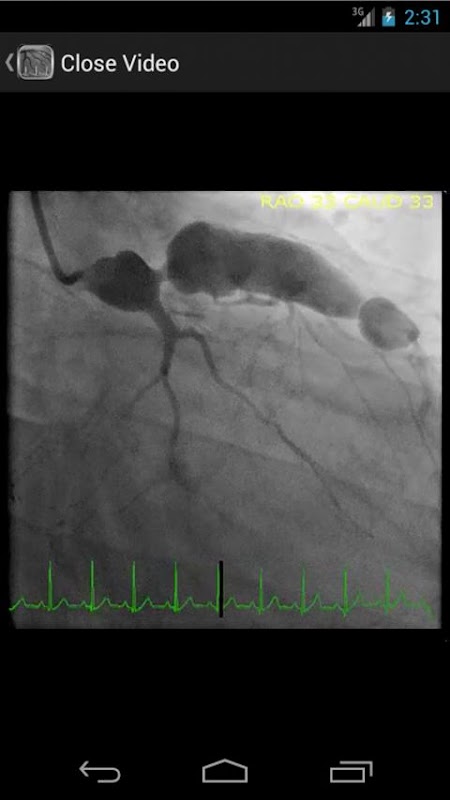

* پایگاه داده قابل جستجو شامل بیش از 30 فیلم (آنژیوگرافی عروق کرونر، ventriculograms، و aortograms) از هر دو یافته های معمول و نادر در آزمایشگاه کاتتریزاسیون قلبی